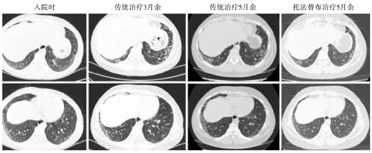

入院时:双肺胸膜下间质性炎症改变,胸壁皮下散在渗出;传统治疗3月余:双肺胸膜下间质性炎症较前减轻,胸壁皮下渗出基本吸收,纵隔出现少量气肿及渗出;传统治疗5月余:双肺改变同前;托法替布治疗5月余:双肺胸膜下间质性炎症较前吸收,纵隔未见气肿及渗出。

患儿诊断为JDM合并ILD,入院后予患儿大剂量甲强龙(500 mg,3 d)冲击治疗,考虑到环磷酰胺对青春前期男孩性腺发育的影响,首先选用足量环孢素(75 mg,日2次,22 d)口服,但患儿出现新发皮疹,双下肢肌力缓解不佳,仍为Ⅲ~Ⅳ级,C反应蛋白升至11.2 mg/L,转氨酶、肌肉酶学及乳酸脱氢酶降而复升,丙氨酸氨基转移酶204 U/L,门冬氨酸氨基转移酶106 U/L,肌酸激酶3 767 U/L,肌酸激酶MB同工酶188 U/L,肌红蛋白1 410.3 μg/L,乳酸脱氢酶517 U/L。故加用环磷酰胺(0.5 g,2 d)冲击治疗,后患儿皮疹消退,四肢肌力恢复至Ⅳ级,转氨酶、乳酸脱氢酶、C反应蛋白降至正常,肌酸激酶降至686 U/L,肌酸激酶MB同工酶降至51 U/L,肌红蛋白降至214.3 μg/L。遂予患儿间隔2周环磷酰胺(0.5 g,2 d)规律冲击治疗共6次,期间予醋酸泼尼松口服,环孢素口服,患儿临床症状一过性好转,无新发皮疹,自觉肌力明显恢复,肌肉酶学、血沉及血清铁蛋白逐渐下降,中间时而间断发热。第6次冲击治疗后,患儿再次出现发热(除外感染),血沉复升,免疫性高炎症C-反应蛋白控制不佳,肺纤维化指标KL-6在治疗期间持续显著升高(图2),复查胸部CT提示双肺胸膜下间质性炎症较前增多,纵隔内新增少许气肿及渗出(图1),肺功能提示限制性通气功能障碍,弥散功能轻度减退,即患儿皮肌炎合并ILD传统治疗疗效不佳,诊断为合并ILD的难治性JDM。遂予患儿加用TOF口服,为防止严重免疫抑制的发生,且已证实环孢素和环磷酰胺的应用疗效不佳,继续应用已无治疗意义,故停用,继续予醋酸泼尼松60 mg(1 mg/kg)口服,按每三周减量5 mg的方式逐渐减量。出院后规律门诊复诊5次,复查肌肉酶学正常,CRP和血沉正常,KL-6持续下降(图2),醋酸泼尼松片逐渐减量至10 mg/d。随诊至2022年5月,患儿病情稳定,复查肺部CT提示双肺胸膜下间质性炎症较前吸收好转(图1),提示TOF治疗有效,激素减量成功,且未见不良反应出现。